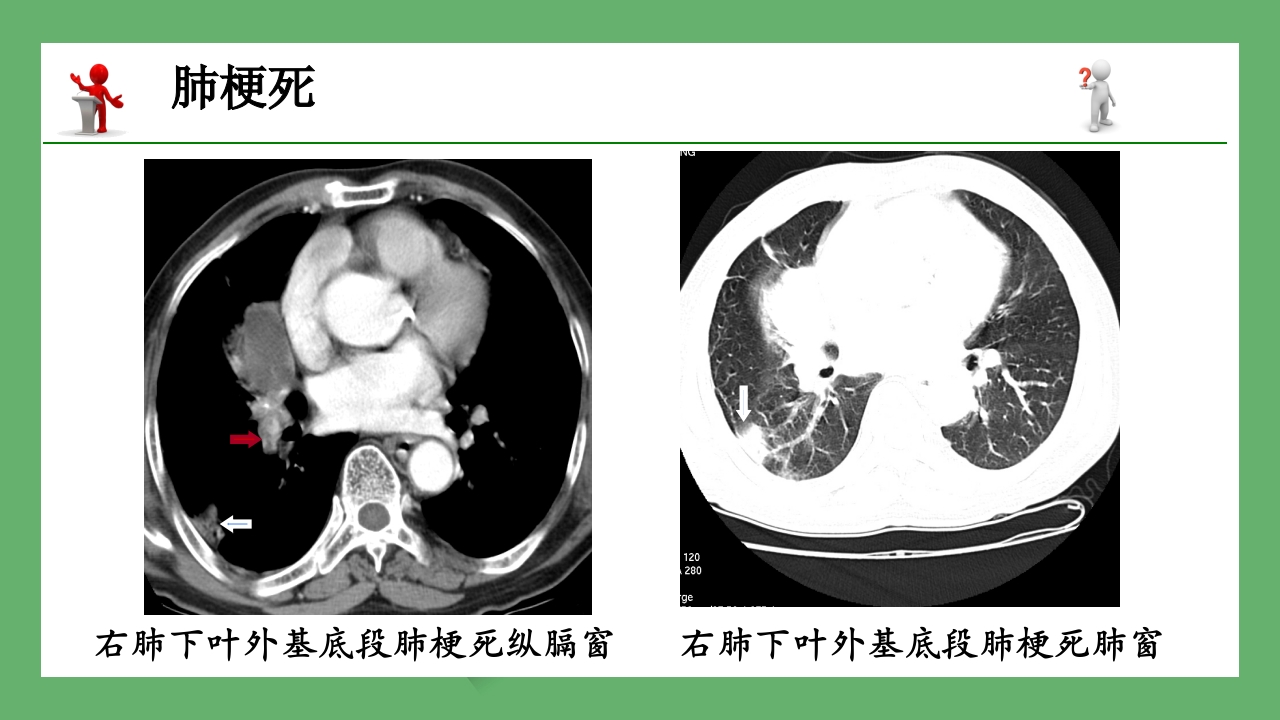

急性肺栓塞的CT表现 授课班级 : 12影像本科班 授课时间 : 20分钟 授课教师 :xxx 主要内容 一 概述 二 病因 三 临床表现 四 急性肺栓塞CT表现 五 一、概述 北医知名教授熊卓为术后离奇死亡 八一女篮队员王凡25岁芳龄被病魔无情带走 共同的杀手:肺栓塞 肺血栓栓塞疾病(pulmonary thromboembolism,PE) 简称肺栓塞,是肺动脉分支被血栓堵塞后引起的相应肺 组织供血障碍。 二、病因 (一)源自下肢的深静脉血栓: 久病卧床 妊娠 外科手术后 心肌梗死 心功能不全 抗血栓因子Ⅲ缺乏 (二)原发于肺动脉的血栓 栓子运行途径与模式图 三、临床表现 PE的常见症状: 呼吸困难 胸痛 咯血 “三联征” 四、急性肺栓塞CT表现 CT血管造影是首选的影像学检查方法! MSCT正常肺动脉显示情况 ...